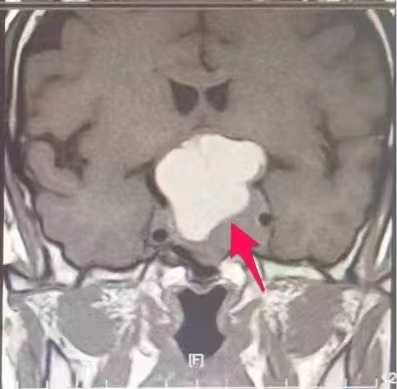

肖女士颅内4厘米的巨型腺瘤。

5月中旬,在家属陪伴下,肖女士到武汉市第五医院就诊。头部磁共振检查结果显示肖女士颅底鞍区存有4厘米的“葫芦”状巨型腺瘤,鞍膈受压上抬,瘤体压迫视神经导致患者视力锐减至失明。